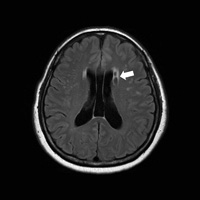

열공성 뇌경색이 나타난 뇌의 MRI 사진/사진=서울대병원제공

서울대병원 가정의학과 이지은 · 박진호, 서울시보라매병원 신경과 권형민 교수팀은 서울대병원 건강검진센터를 방문한 2326명의 뇌 MRI와 혈액검사 등을 활용, 인슐린저항성과 열공성 뇌경색의 상관성을 분석했다. 열공성 뇌경색은 뇌의 소혈관이 막혀 생기는 뇌경색으로 주로 무증상 뇌경색을 초래하는 질환이다.